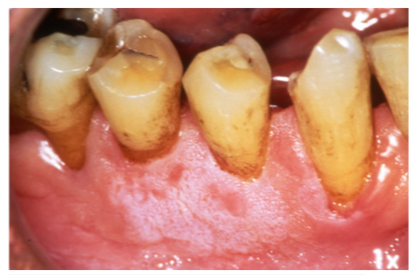

Figure 10 - Gingival irritation and tobacco stained teeth Courtesy of Dentalcare.com

Figure 10

The most notable health consequences associated with spit tobacco use are those seen in the oral cavity. These effects can be recognized by the patient as well as the clinician and provide excellent opportunities to educate the user in the dangers of the tobacco use. Spit tobacco use causes serious short-term health consequences among young people. These consequences include halitosis, staining, abrasion of the teeth, gingivitis, gum recession, dental caries, and tooth loss.

Tooth loss is more common among spit tobacco users than nonusers. This loss is a result of several factors including poor oral hygiene, extensive decay, and destructive periodontitis. Focal gingival recession with periodontal attachment loss and bone erosion occurs frequently on the facial surfaces of the teeth where the tobacco is held. This recession is a result of the irritation caused by the toxic chemicals and abrasives found in spit tobacco. It is not uncommon to find substantial amounts of root surfaces exposed at the tobacco placement site. With the root surface exposed, there is increased risk of hot and cold sensitivity and root decay. While gingivitis may be present, bleeding is less common because of the vasoconstriction properties of nicotine. Instead, the heavy spit tobacco user will likely develop gingival swelling and bleeding as a result of poor oral hygiene.

Additional characteristics of long term spit tobacco use are stained teeth and halitosis. The tobacco and the juice produced can penetrate into the tooth enamel and restorative material, resulting in a brown or yellow darkening of the teeth. These stains, in the presence of poor oral hygiene, can also result in a dark brown line along the gingival margins of the affected teeth. The pitting of tooth surfaces caused by the abrasives in the tobacco results in intrinsic staining. Halitosis is the most commonly recognized negative consequence of spit tobacco use. It is a result of the constant presence of tobacco juice in the user's mouth. In addition, the need to continually spit out excess juice and saliva is offensive and unhygienic. Spit tobacco users often find pieces of tobacco lodged between their teeth, in the buccal folds, and on the lips.

The abrasives found in spit tobacco can also wear away portions of the occlusal/incisal surfaces of the teeth resulting in a weakening and eventual chipping of those surfaces. The abrasives also irritate the gingival tissue, allowing for more efficient absorption of the carcinogenics and nicotine found in the tobacco. As a result of the chemicals and sodium in spit tobacco, users suffer a lessening of their senses of taste and smell. This can lead to unhealthy eating habits. Excess sodium may augment the effect of nicotine on elevating blood pressure.